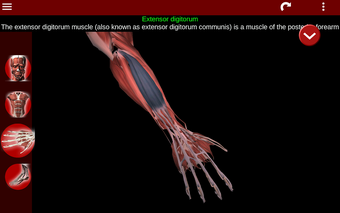

Esta herramienta educativa proporciona una descripción de cada músculo del cuerpo humano, así como un modelo tridimensional del sistema muscular. Con sólo tocar con el dedo, la aplicación revelará la información pertinente.

Los usuarios pueden hacer zoom sobre el músculo, así como elegir si ocultar o mostrar los datos. La orientación puede ser horizontal o vertical, según convenga más.